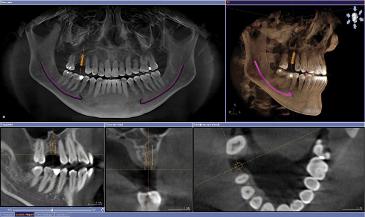

Um auch bei speziellen Fragestellungen und schwierigen Ausgangssituationen eine genaue Diagnose stellen zu können, eine exakte Implantatplanung gewährleisten zu können oder einen Eingriff sicher vorbereiten zu können, bieten wir in unserer Praxis die Digitale Volumentomographie (DVT) als hochmodernes Röntgenverfahren an.

Bei der Digitalen Volumentomographie handelt es sich um ein dreidimensionales Röntgenverfahren, welches durch eine spezielle Kegelstrahltechnik besonders strahlungsarm ist. Hierbei können die Kieferknochenverhältnisse millimetergenau vermessen werden.

Implantatoperationen lassen sich millimetergenau planen. Knochenangebot und Strukturen werden vor der Operation genau analysiert, um maximalen Operationserfolg zu erzielen.